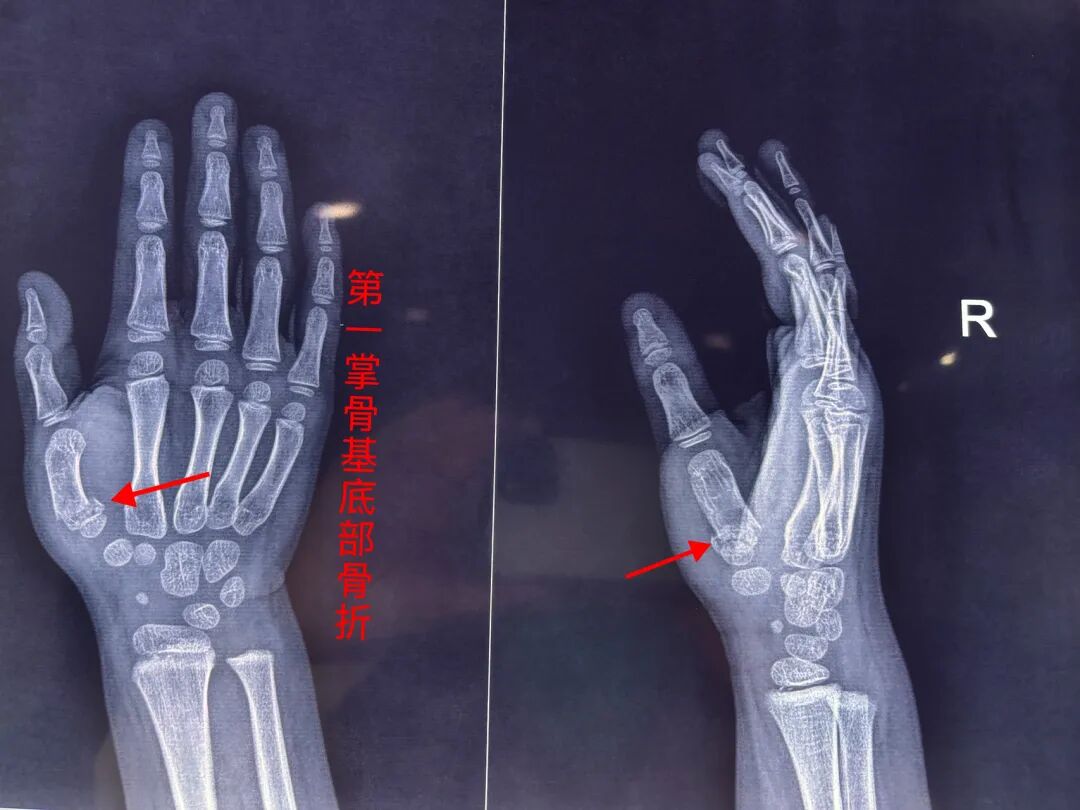

患儿骑自行车时摔倒致拇指受伤,拇指活动受限:拇指无法正常完成外展、主动、被动活动受限。